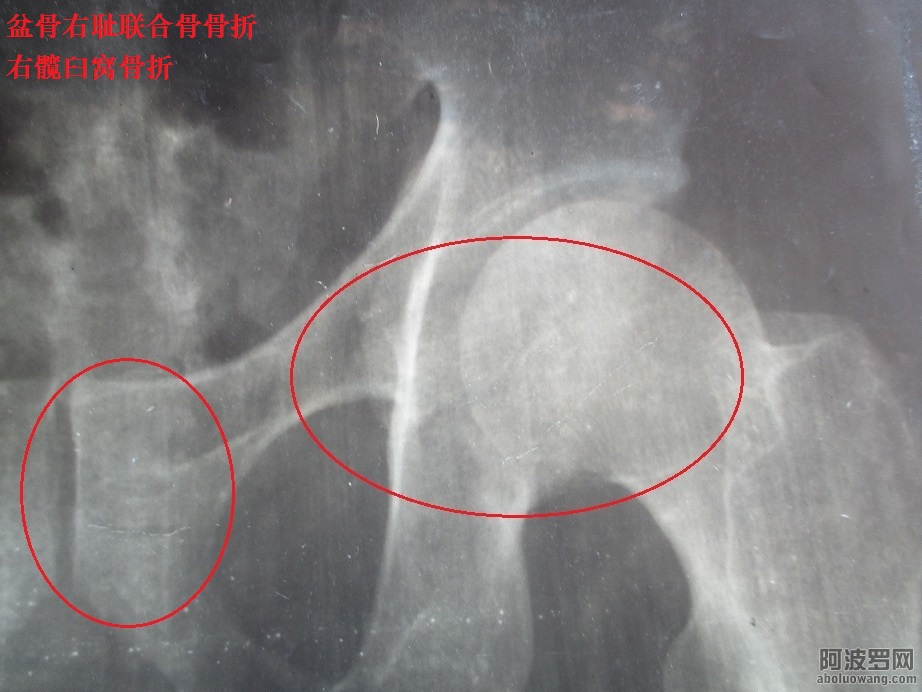

因爲這事件,被惠州市政府長年累月絞盡腦汁日夜不停歇地整,父母心髒都出現相當問題,我母親也相續住院了,心髒出現病患,她特別向我說明是惠州政府長期整她産生的;●而我每分鍾心跳加快20次或者以上,明顯感到心悸、胸悶、不適···【惠州市政府長年累月精神虐待暴力摧殘,導致舉報滔天罪行者全家人患心髒病】

2:惠州市政府長期暴力摧殘精神虐待、殘酷迫害導致舉報人全家都患了心髒病。